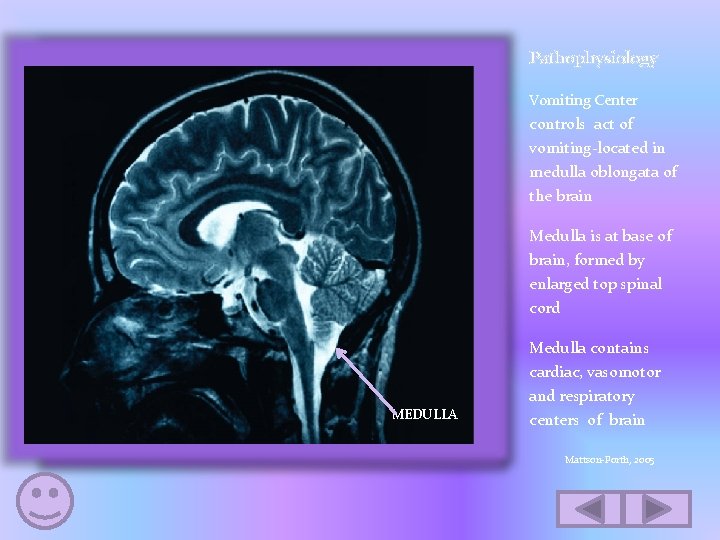

Pathophysiology Vomiting Center controls act of vomiting-located in medulla oblongata of the brain Medulla is at base of brain, formed by enlarged top spinal cord MEDULLA www. anomalocaris. net Medulla contains cardiac, vasomotor and respiratory centers of brain Mattson-Porth, 2005